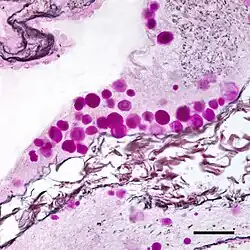

Micrograph of corpora amylacea (purple spheres) in the brain of a person with Alzheimer's disease. Combined Periodic acid-Schiff and silver stains. Bar = 50 microns (0.05 millimeters).

The composition and appearance of corpora amylacea can differ in different organs.[3] In the prostate gland, where they are also known as prostatic concretions, corpora amylacea are rich in aggregated protein that has many of the features of amyloid, whereas those in the central nervous system are generally smaller and do not contain amyloid.[3] Corpora amylacea in the central nervous system occur in the foot processes of astrocytes, and they are usually present beneath the pia mater, in the tissues surrounding the ventricles, and around blood vessels.[2] They have been proposed to be part of a family of polyglucosan diseases, in which polymers of glucose collect to form abnormal structures known as polyglucosan bodies.[3] Polyglucosan bodies bearing at least partial resemblance to human corpora amylacea have been observed in various nonhuman species.[3]